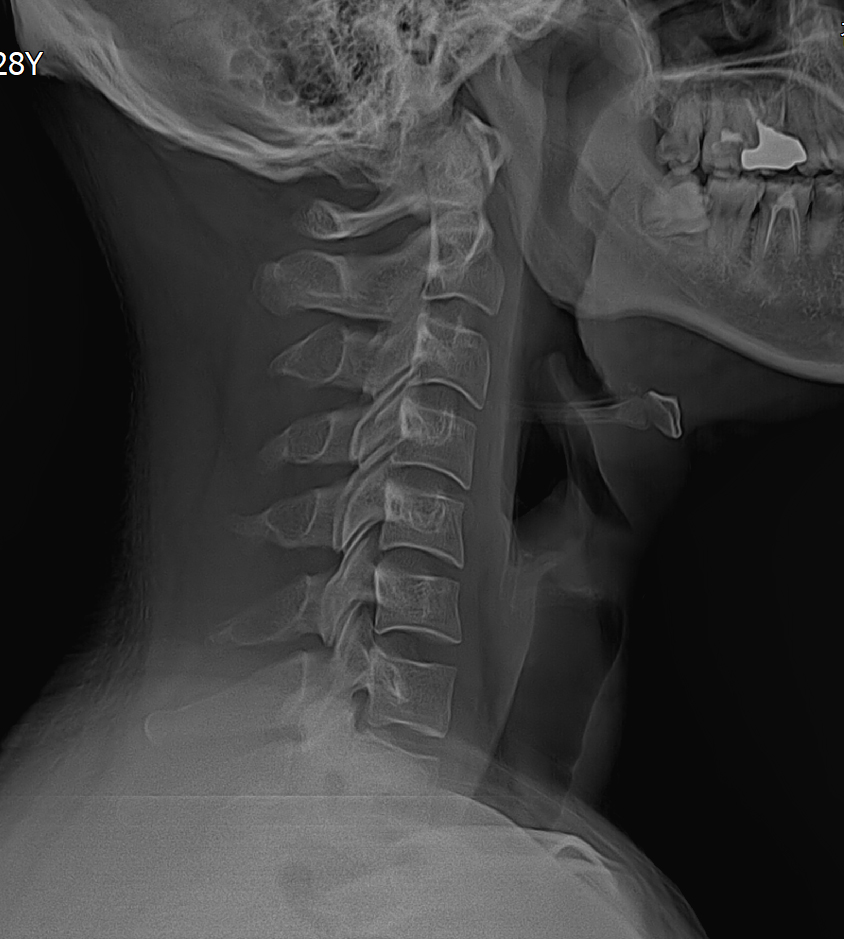

· 옆에서 봤을 때 경추는 C형이어야 정상이나, 목뼈가 잘못된 자세 등으로 일자형 변형된 질환 입니다.

• 정상 목 사진

• 일자 목 사진